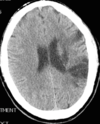

What are the different mechanisms for ischemic strokes?

What are symptoms of a middle cerebral artery stroke?

Contralateral (weakness, sensory loss, Visual field defect)

Gaze preference towards the side of the sroke

brocas abd Wernickes aphasia

left spatial neglect if on right parietal lobe